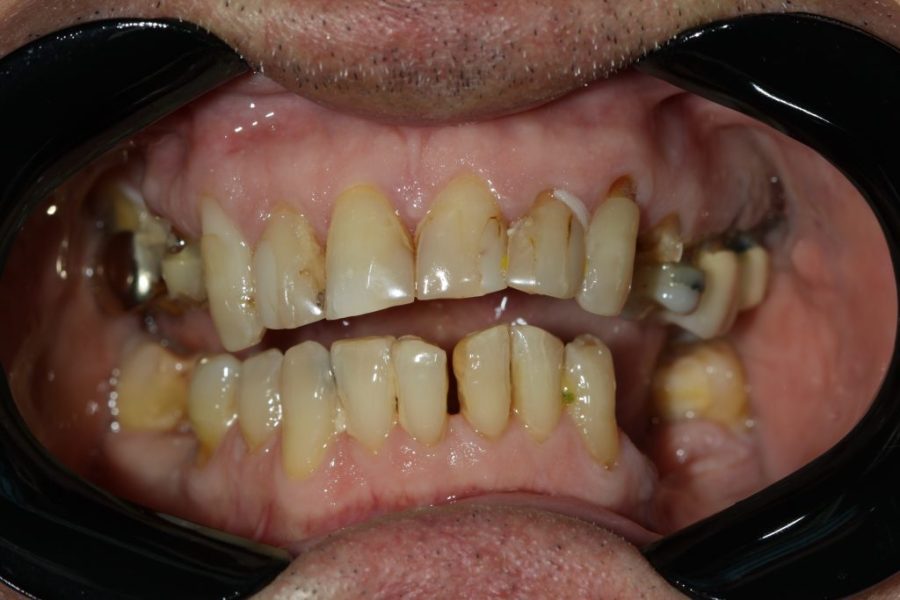

Henry’s Story: A Full Smile Makeover

Henry’s broken teeth were impacting his confidence. With a combination of root canal therapy, laser gum surgery, crowns, and dentures, we restored his smile over four weeks. Now, his family and grandchildren are thrilled with his transformation.